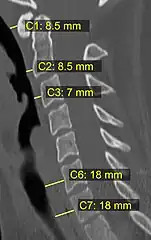

CT scan or X-ray images are evaluated for the presence or absence of directly visible fractures. In addition, indirect signs of injury by the vertebral column are incongruities of the vertebral lines,[11] and/or increased thickness of the prevertebral space:[12]

- 1 2 Rojas, C.A.; Vermess, D.; Bertozzi, J.C.; Whitlow, J.; Guidi, C.; Martinez, C.R. (2009). "Normal Thickness and Appearance of the Prevertebral Soft Tissues on Multidetector CT". American Journal of Neuroradiology. 30 (1): 136–141. doi:10.3174/ajnr.A1307. ISSN 0195-6108. PMC 7051716. PMID 19001541.